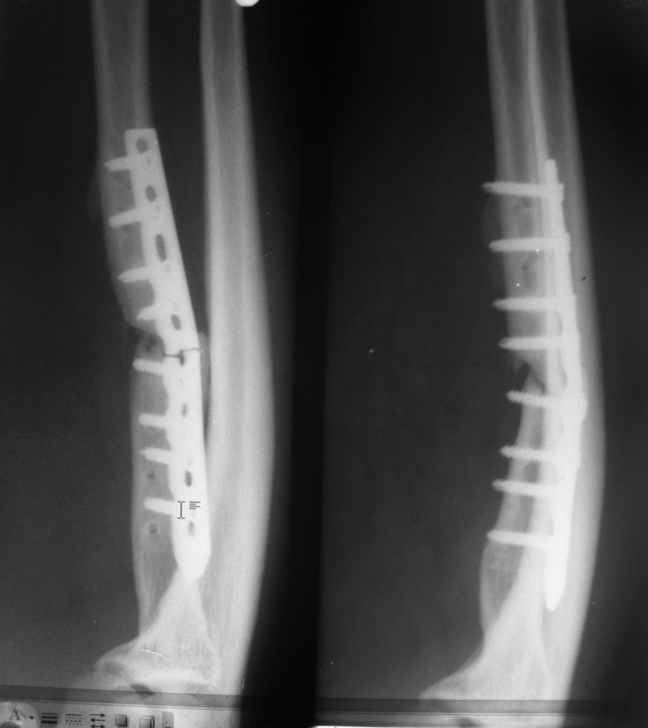

Глубокоуважаемые коллеги!Помогите определиться с объёмом оперативного лечения несросшегося перелома лучевой кости

Мужчина средних лет, крепкого телосложения, с высокими физическими требованиями. Травма 2 года назад. Оперирован дважды, сразу после травмы и в апреле2010 по поводу перелома пластины. В настоящее время вновь сломана пластина, боли, нарушение функции. Теперь его лечить предстоит мне. Дефекты предшествующей операции в общем понятны. Пожалуйста, помогите определится с оптимальным вариантом операции, пластики.Заранее благодарен, Кирилл